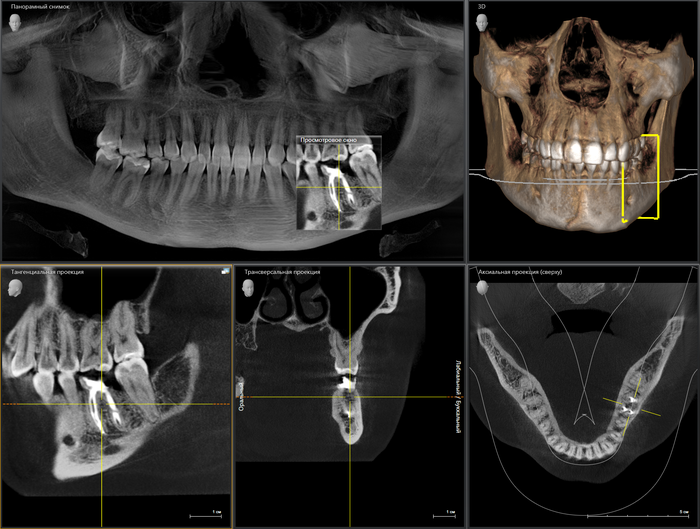

Ниже, на панорамном снимке зубов, мы наблюдаем критичную убыль костной ткани вокруг имплантатов на верхней челюсти.

Оранжевая пунктирная линия - было,

красная - стало.